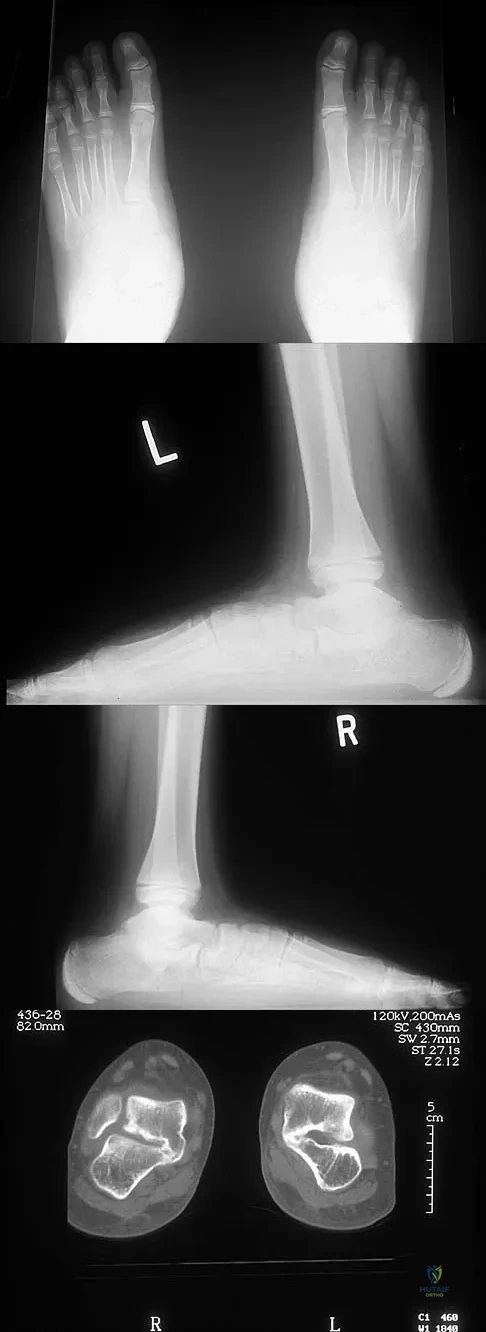

A 12-year-old boy has had progressive pain and flatfeet for the past year. Pain is increased with weight-bearing activities. Examination reveals that subtalar motion is absent. On standing, the patient has obvious hindfoot valgus and loss of the normal arch bilaterally. Plain radiographs are shown in Figures 43a through 43c, and a CT scan is shown in Figure 43d. What is the most likely diagnosis?

A 45-year-old man has persistent hindfoot pain that is aggravated by weight-bearing activities. History reveals that he sustained a calcaneus fracture 2 years ago, and he underwent a subtalar fusion 1 year ago. Examination reveals tenderness in the sinus tarsi and across the transverse tarsal joint. A plain radiograph and a CT scan are shown in Figures 24a and 24b. A technetium Tc 99m bone scan reveals uptake at the subtalar joint and at the transverse tarsal joints. Management should now consist of